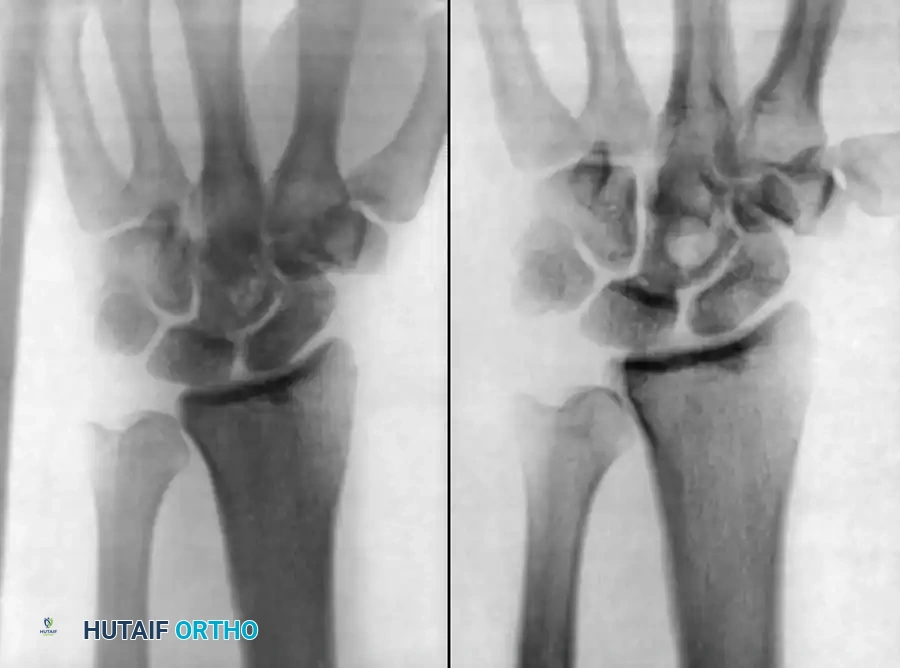

Figure 18-10: Radiographic presentation of recurrent Histoplasmosis in the wrist, demonstrating profound lytic destruction of the carpal rows and distal radius articular surface.

3. Radical Debridement: Grossly infected and necrotic carpal bones are excised. In cases of severe destruction (as seen in Fig 18-10), a proximal row carpectomy or complete carpectomy may be necessary.

4. Reconstruction: Depending on the extent of bone loss and infection eradication, a delayed total wrist arthrodesis using a dorsal spanning plate and robust iliac crest autograft is performed once the fungal burden is cleared via systemic antifungals (itraconazole).